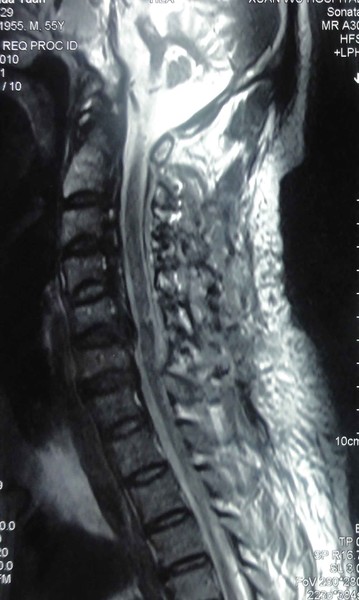

当地医院建议患者进行手术治疗,患者未接受手术治疗建议,保守治疗。于入我院1日前,不慎跌倒。出现四肢无力,大小便功能障碍等症状。来我院就诊,急诊进行颈椎核磁共振检查,发现急性颈髓损伤。如下图:

图2 患者颈椎MRI显示,患者脊髓受到明显压迫,脊髓严重损伤